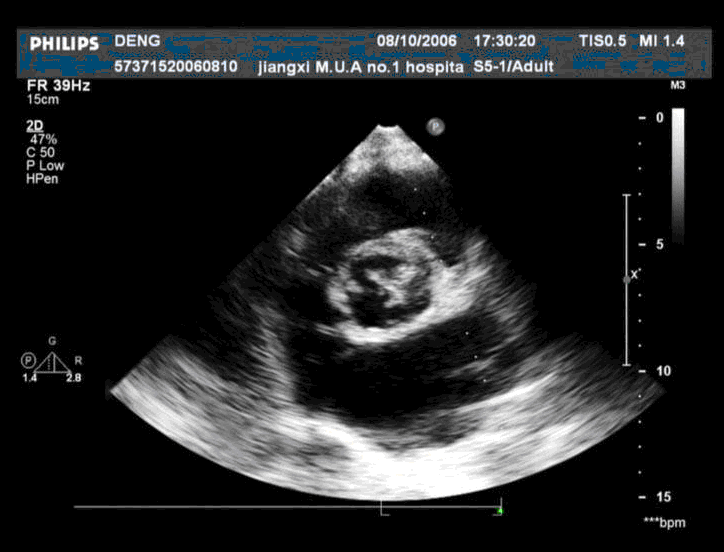

患者,男,50岁,发热半月余,全身不适,乏力,食欲缺乏。根据超声心动图,最可能的诊断是 CF20160315_19.gif CF20160315_20.gif CF20160315_21.gif CF20160315_22.gif

• B.感染性心内膜炎